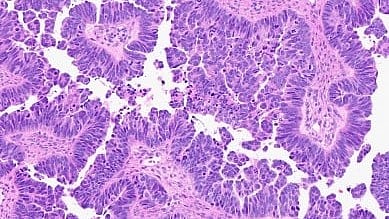

High-grade serous carcinoma, the most common type of ovarian cancer, usually begins in the fallopian tube, before spreading to the ovaries and other pelvic organs. The cancer is typically discovered at an advanced stage and becomes resistant to current chemotherapies. Its underlying genetics are complex, with multiple genetic alterations and instabilities. One of the genes involved is CDK12.

“It is very important to credential the model systems by showing they recapitulate key features of their human counterparts, a process that is also very time-consuming,” said co-senior study author Cho, Peter A. Ward Professor of Pathology, co-director of the Rogel Cancer Center’s cancer genetics program, and director of gynecologic pathology at Michigan Medicine.

“These features include not only cell of origin and appearance under the microscope, but also timing of tumor development, underlying genetics, acquired genetic alterations and gene expression profiles, tumor microenvironment (including the immune cell components) and other aspects of biological behavior,” she said.